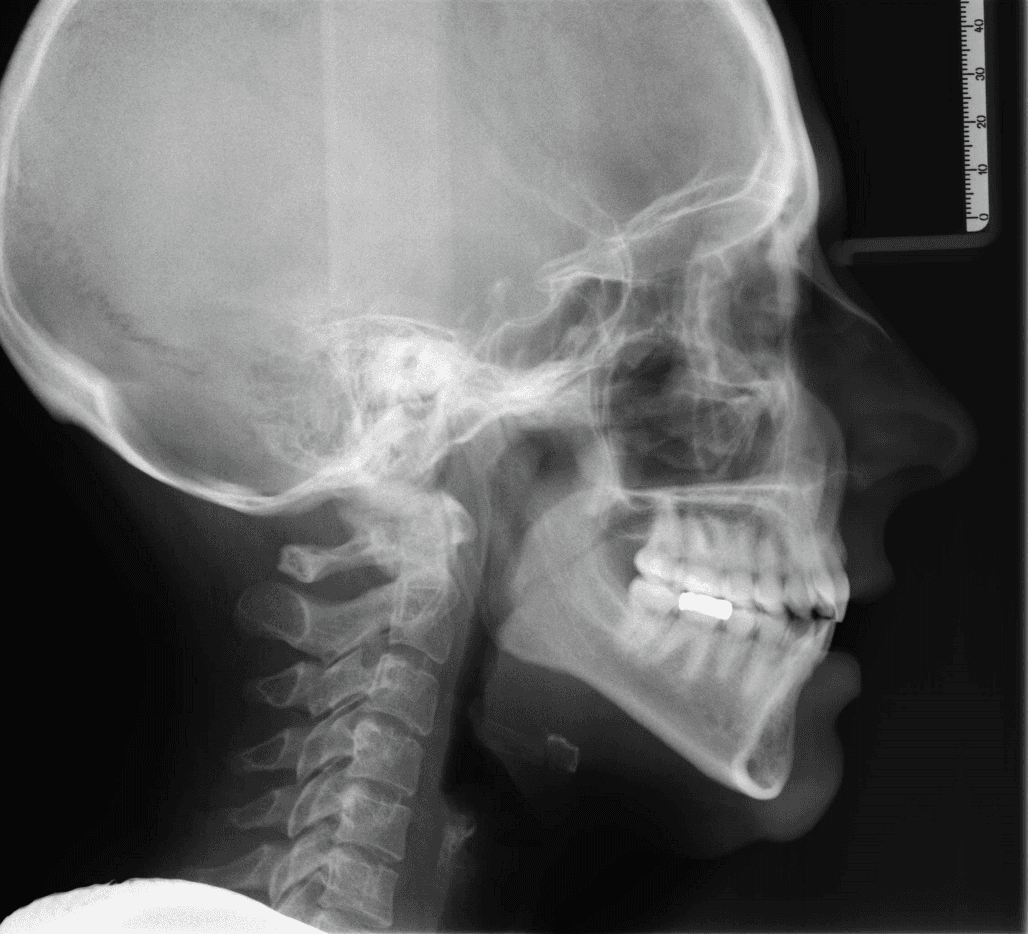

X-RAYS